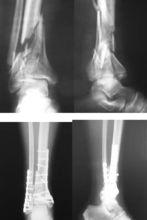

外傷後踝部腫脹、畸形、不能負重,追問受傷時的情況來判斷是否有軸向暴力發生作用。結合X線片或CT檢查,Pilon骨折的診斷並不困難。X線片包括:(1)踝關節正、側位像;(2)外鏇斜位像,可很好地顯示脛骨前內側和後外側關節面骨折情況;(3)對側踝關節X線片,既可以排除骨折的存在又可以作為復位的模特。CT片能夠很好的顯示骨折的形態、骨折塊的數量以及移位的程度,矢狀位和冠狀位重建圖像能夠顯示出事實上更為複雜的骨折情況。在評價骨折的移位程度、術前制定的治療方案以及指導手術治療方面,CT較普通X線片有明顯的優勢。